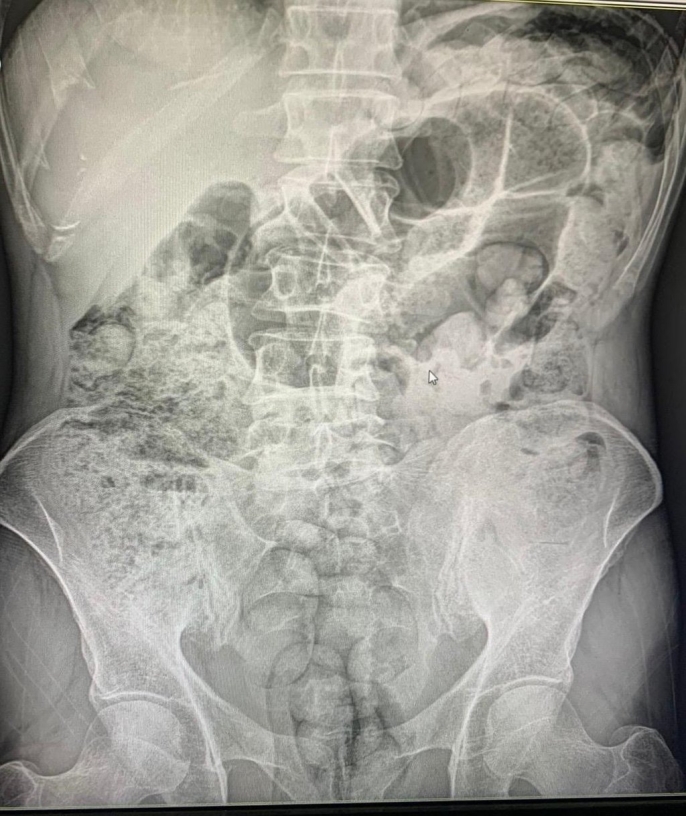

Siirt'te gerçekleştirilen operasyonda, batı illerine uyuşturucu sevkiyatı yapmaya çalışan İran uyruklu 4 şahıs yakalandı. Şüphelilerin mide boşluklarına gizledikleri toplam 1 kilo 597 gram uyuşturucu madde, 10 günlük hastane süreci ve cerrahi müdahale sonucunda çıkarıldı.

Şüphelilerin mide ve bağırsaklarında bulunan uyuşturucu maddelerin çıkarılması için 10 gün süren bir hastane süreci başlatıldı. Bu süreç sonunda cerrahi müdahalelerle toplam 119 paket halinde 1 kilo 597 gram uyuşturucu madde ele geçirildi. İşlemlerinin ardından adliyeye sevk edilen 4 şüpheli tutuklanarak cezaevine gönderildi.